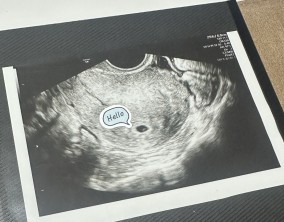

믿음 끝에 찾아온 첫 기적

의료진분들의 따뜻한 말 한마디와 친절한 행동 하나하나가 힘든 난임 치료 과정에서 큰 도움이 되었습니다. 그 진심 어린 마음이 앞으로도 많은 난임 부부들에게 변함없이 전해지…